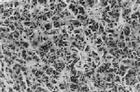

病理說明

幾乎所有胰島素瘤位於胰腺實質內,異位瘤往往靠近胰腺,但很罕見。據國外Stefanini等報告及綜述世界文獻中951例資料,此組腫瘤均勻分布於胰頭,體及尾部。國內所見,大致與國外相似。腫瘤直徑從0.5cm至>0.5cm,其中87%為0.5~5cm,國內報導最小腫瘤僅0.2cm,大多患者(約65%)腫瘤直徑小於1.5cm,腫瘤大多呈灰白色或紫紅色,邊界清楚但大多無包膜,質較正常胰組織為軟,表面不平,血供豐富,瘤體小,位置隱蔽,手術時難以發現,尤其是胰頭和鉤突部的腫瘤。如腫瘤大並有鈣化則提示惡性可能,惡性腫瘤發現時多已淋巴結轉移,肝轉移最多見,其次為肺和骨轉移。腫瘤組織切面上呈結締組織多寡不一,內分泌細胞組織中有小管樣組織,有時呈澱粉樣變,瘤細胞中含小圓膠體,與其他分泌肽類的瘤細胞不易區別。近年來發現,在胰島B細胞瘤中,除了胰島素外,還含有胰升糖素,胃泌素,胰多肽,生長抑素等多種肽類物質,電鏡下瘤細胞大致可分為四類,典型B細胞中含典型B顆粒,分泌胰島素最多,約占瘤細胞的半數;其次為部分典型B細胞,部分不典型B細胞,其中含A、D細胞顆粒,分泌胰島素較少;第三類為不典型細胞,分泌胰島素更少,但胰島素原較多;第四類幾乎無顆粒,系癌腫樣細胞,但亞微結構示高功能活動,其分泌物可能主要為胰島素原或其類似物(但有報導用螢光抗體法並未證明這一點)。總之,腫瘤細胞的形態和分泌功能與分化程度有關,分化愈成熟者分泌胰島素愈多,愈不成熟者愈少,且同時有其他分泌可能。鏡下癌細胞排列呈索狀或腺樣,較小,胞漿透明而核染色較深,呈方形或多角形,細胞形態不一,核分裂常見,且有軟組織浸潤。胰島B細胞增生有瀰漫性及結節狀兩種,有時伴微小腺瘤。多發性內分泌腺瘤者有甲狀旁腺,垂體,腎上腺,甲狀腺腺瘤的各種組合,尤以前三者為多見。